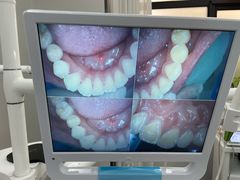

• 牙博士口腔品牌连锁(杨浦店)

• -牙博士口腔品牌连锁(杨浦店)

奶酪红烧桃子 | 22-08-09